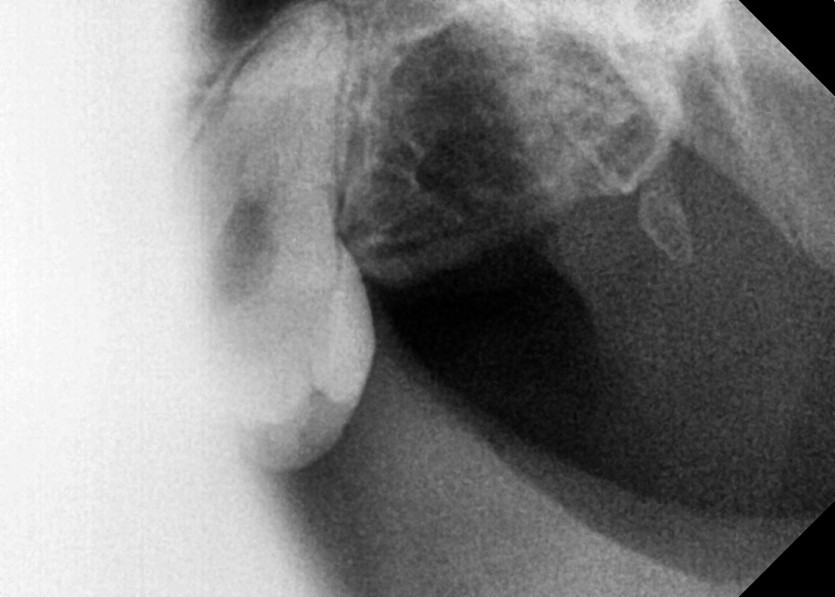

#18,28,38,48 사랑니 발치

구강 외과 전문의가 당일 발치했습니다.